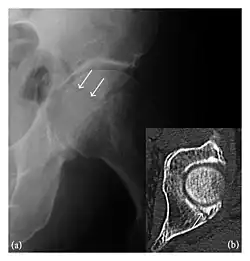

Occult osseous injuries may result from a direct blow to the bone by compressive forces of adjacent bones against one another or by traction forces during an avulsion injury. Lesions in the tibial plateau, hip, ankle, and wrist are often missed. In a tibial plateau fracture, any disruption of the posterior and anterior cortical rims of the plateau should be sought. Impaction of subchondral bone will appear as an increased sclerosis of the subchondral bone (Figure 1). In the hip, posterior acetabular fractures also present subtle radiographic findings. The acetabular lines should then be carefully examined keeping in mind that the posterior rim, which is harder to see on X-rays, is more frequently fractured than the anterior rim (Figure 2). In the wrist, detection of carpal bone fractures is often challenging, with up to 18% of scaphoid fractures radiographically occult. Carpal fractures, especially the scaphoid, are associated with the risk of avascular necrosis. In apparently normal wrist radiographs from symptomatic patients, if there is history of a fall on an outstretched hand with pain in the anatomic snuffbox, suggesting scaphoid injury, the initial examination with posteroanterior, lateral, and pronation oblique views must be complemented by other specific views such as supination oblique and the "scaphoid" view A careful examination of cortices for evidence of discontinuity or offset and cancellous bone for lucency is necessary (Figure 3).[1]

Figure 1: A 56-year-old woman presenting with left knee pain after a fall. (a) Initial anteroposterior radiograph was considered normal, however, subtle cortical disruption of the anterior rim of the medial tibial plateau, medial to the tibial spine, is noted (arrow). (b) Coronal T1-weighted MRI confirms the cortical disruption (arrow) and shows extensive fracture through the proximal tibia. (c) Coronal proton density-weighted image with fat saturation shows extensive edema in the subchondral bone. Note also hypersignal adjacent to the medial collateral ligament corresponding to a grade I sprain (arrowheads).[1]

Figure 3: A 26-year-old man presenting with wrist pain after being assaulted. (a) Initial anteroposterior radiograph shows a subtle linear lucency within the scaphoid extending to the scaphocapitate articular surface that was overlooked (arrow). (b) Initial "scaphoid" view was negative. (c) Followup anteroposterior radiographs, 12 days later, shows obvious scaphoid fracture (arrows).[1]

Figure 4: Dorsal triquetral fracture of the left wrist in a 30-year-old man after a trauma. (a) Anteroposterior radiograph shows a normal appearance. (b) Lateral radiograph of the same wrist demonstrates a chip fracture off the dorsal aspect of the triquetrum (arrow).[1]